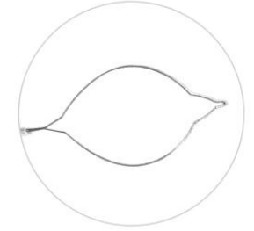

| Plasma Loop Cutting Electrode: The plasma loop cutting electrode is used for precise tissue cutting in surgical procedures. It is designed with a loop-shaped configuration that enables controlled and accurate tissue incision. The electrode delivers plasma energy to the loop, allowing it to efficiently cut through tissues. It is commonly employed in procedures such as tissue excision, tumor resection, or tissue biopsy, where precise and controlled cutting is required. |  |